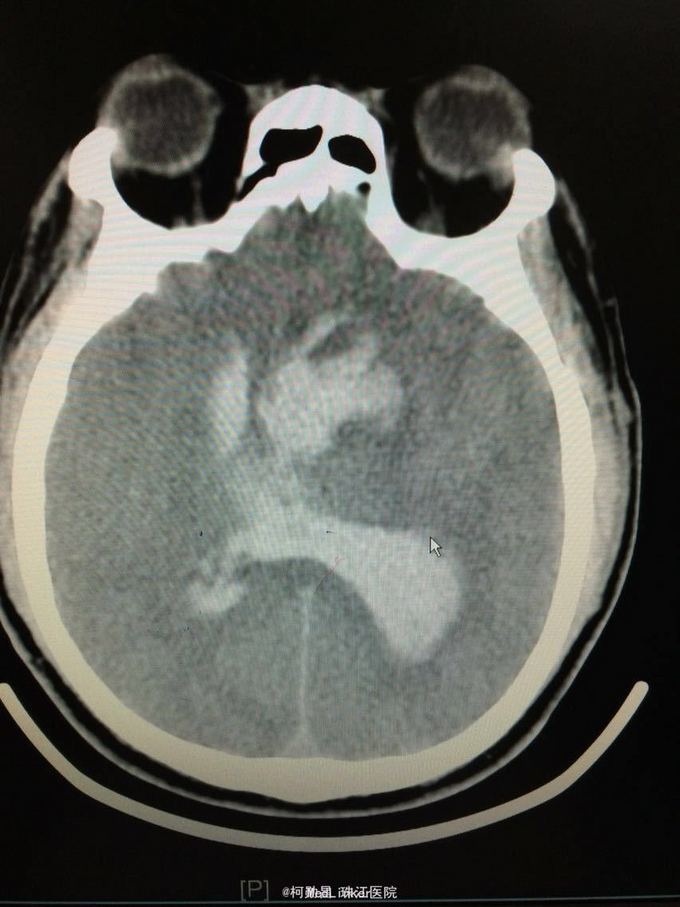

主诉:突发意识障碍4小时 病史:患者57岁男性,入院前一天晚上突发意识不清,伴呕吐胃内容物多次,无肢体抽搐等,随即由家人呼叫120送至我院,急诊行头颅CT提示左侧基底节区出血破入脑室。既往高血压病史10多年

查体:神志不清,双侧瞳孔散大,对光反射消失,四肢肌张力正常,肌力无法检查 辅助检查:头颅CT提示左侧基底节区出血破入脑室

诊断:左侧基底节区出血并破入脑室 处理:急诊行侧脑室钻孔外引流术,术后并予积极抢救,最终抢救无效死亡

随访:患者最终死亡。 讨论:该患者属于典型的高血压性脑出血,且出血量多,预后不良。壳核和丘脑是高血压性脑出血的两个最常见部位。典型可见三偏体征(病灶对侧偏瘫、偏身感觉缺失和偏盲等),大量出血可出现意识障碍,也可穿破脑组织进入脑室,出现血性CSF,直接穿破皮质者不常见。